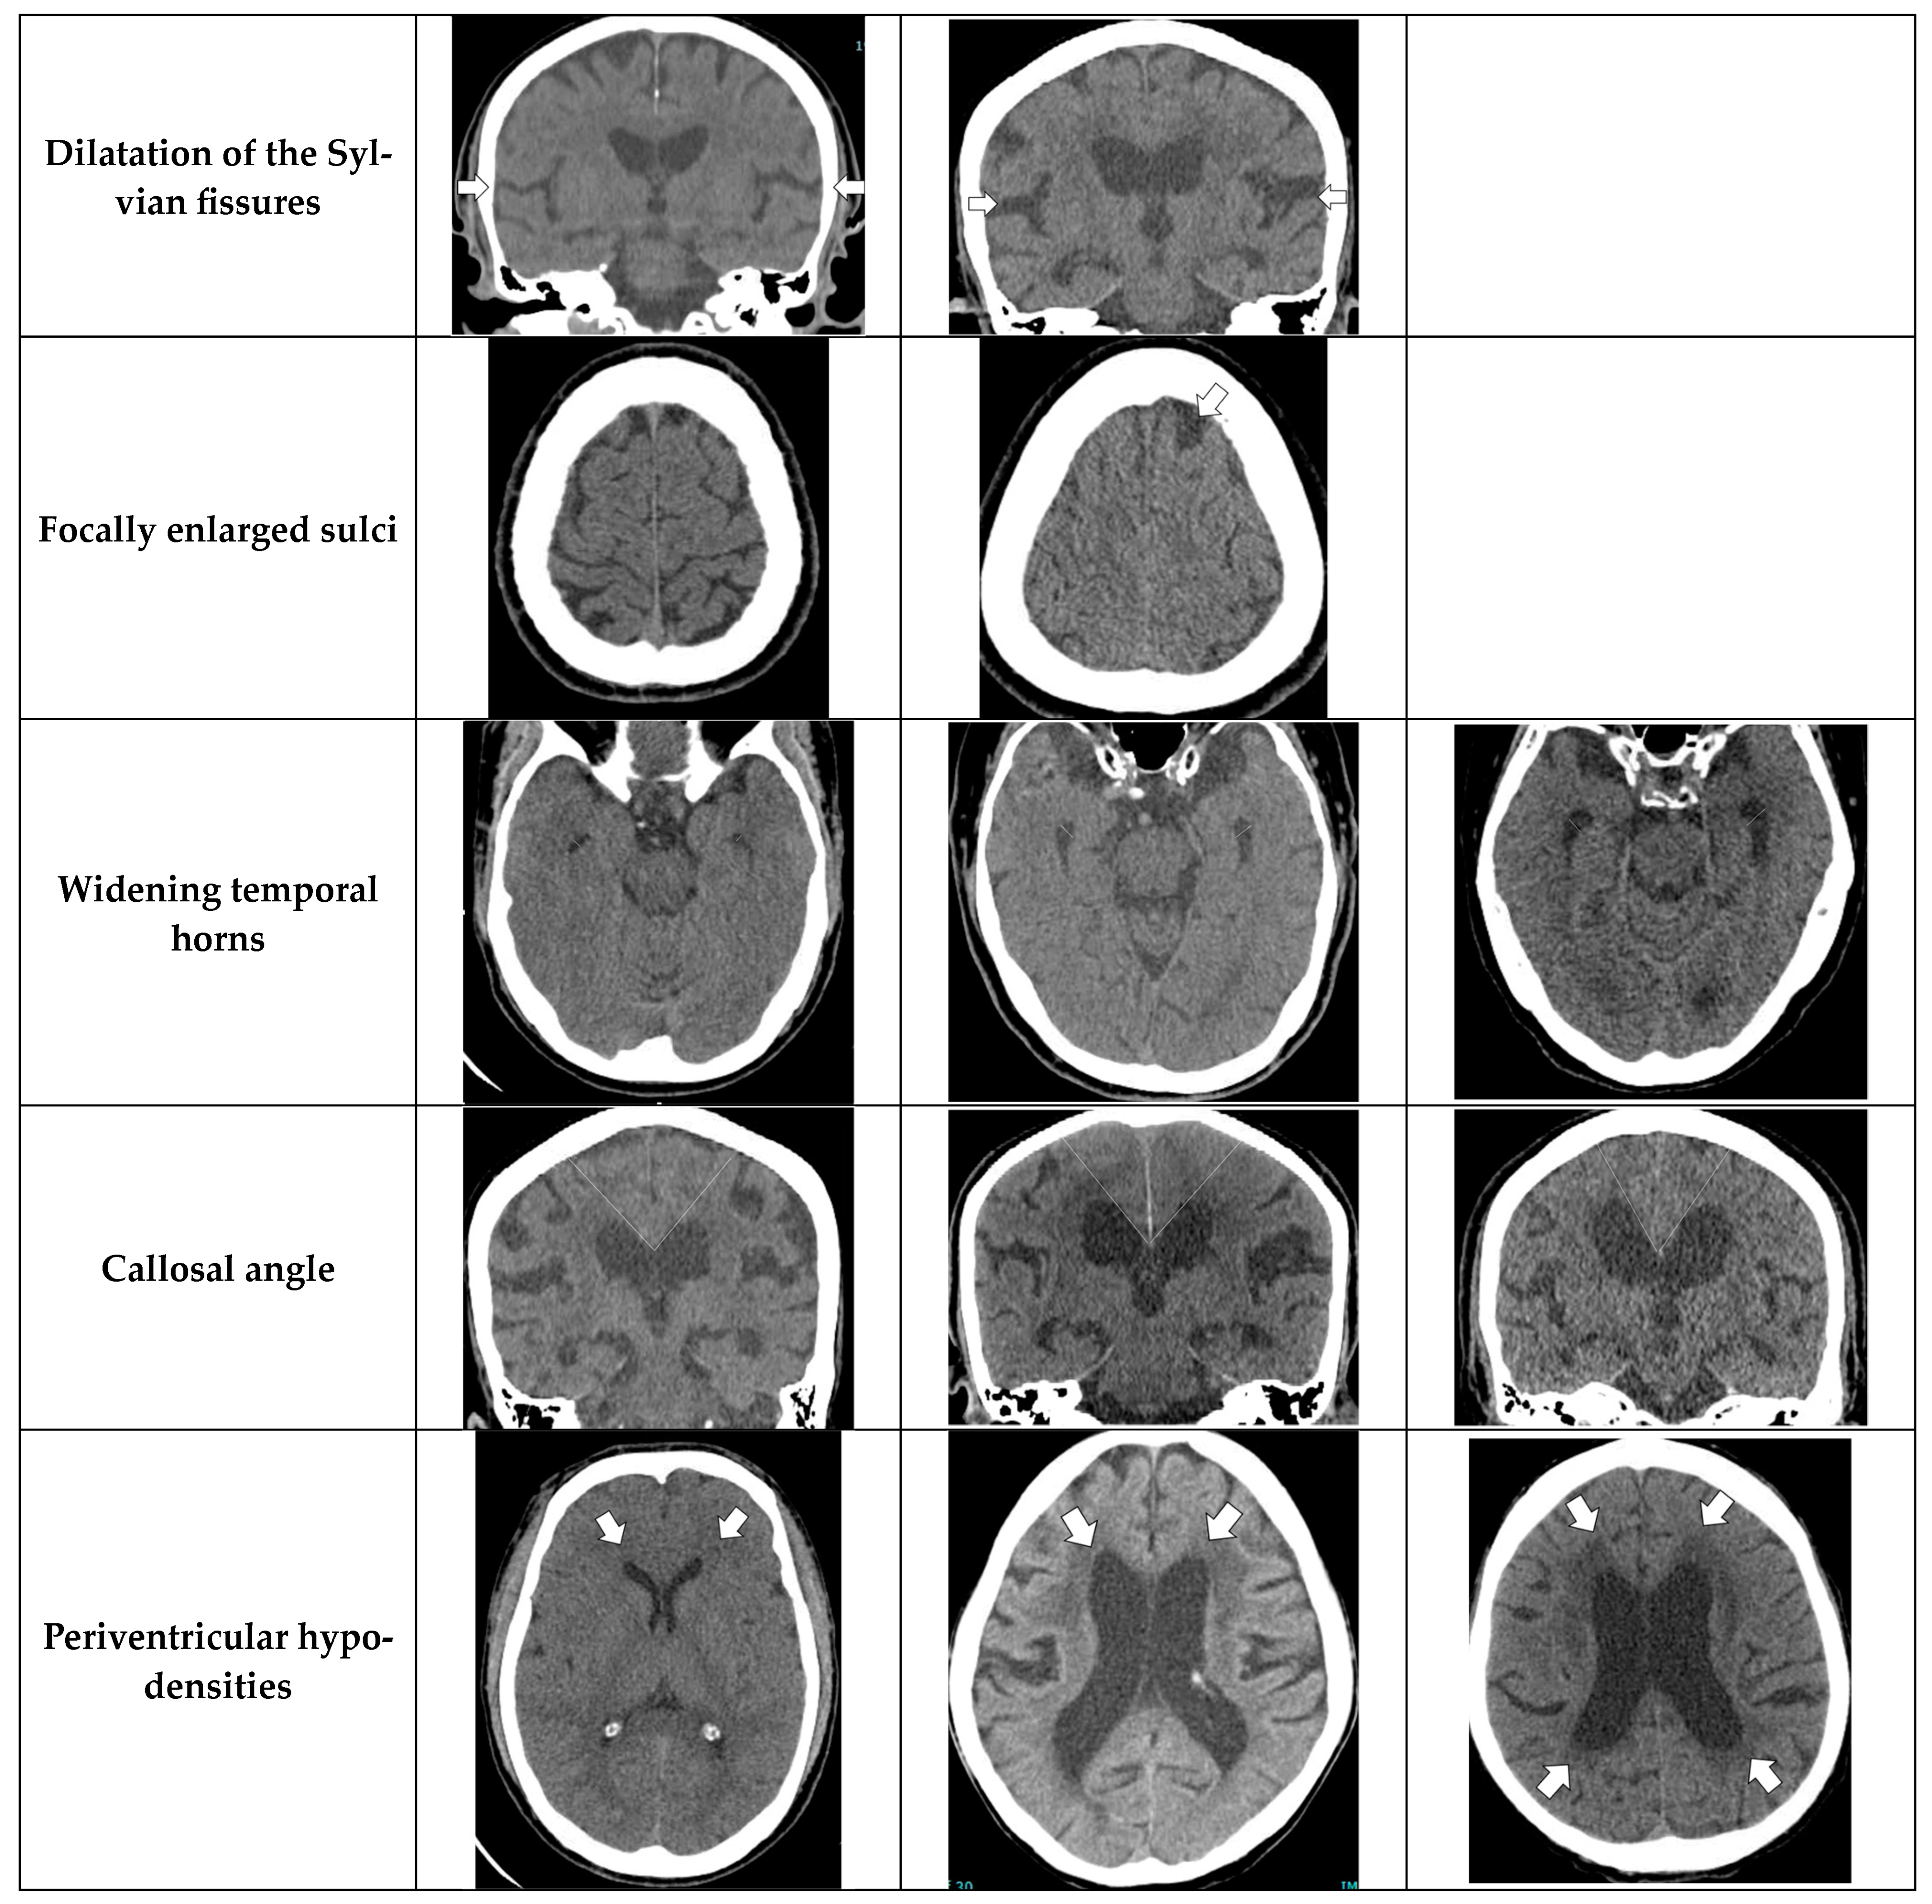

- Dilation of the Sylvian fissures: Reported as present or not present in the coronal plane compared with surrounding sulci [11].

- Focally enlarged sulci: Compared with surrounding sulci, usually found in coronal or axial planes [12].

- Temporal horns: Reported as mean width of the right and left side, measuring in the axial plane [11].

- Callosal angle: Angle between the lateral ventricles in the coronal plane through the posterior commissure perpendicular to the intercommissural plane [13].

- Periventricular hypodensities: Along the lateral ventricles graded as not present, present as a cap around frontal horns or confluently extending around the lateral ventricles [14].